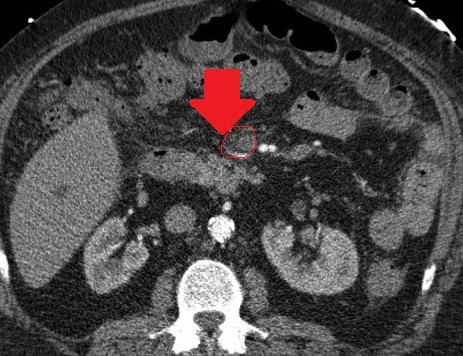

Mesenteric root infiltration — Absolute contraindication for cytoreductive surgery (Courtesy Dr. V. Penopoulos)